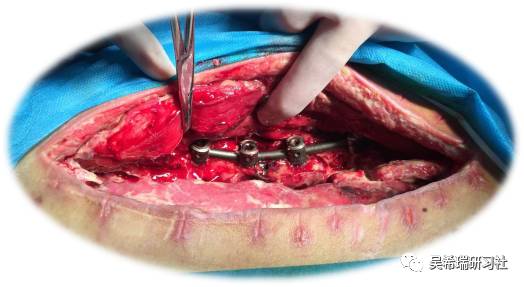

髌骨手术后继发感染40天髌韧带外露

TIPS:清创后再固定伤口用抗生素骨水泥感染得到控制后皮肤牵张闭合伤口2个月内手法松解关节,骨牵引维持5天